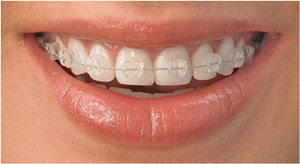

2.陶瓷托槽矫治技术

详细介绍:透明陶瓷治疗器由坚固透明的生物陶瓷材料——航天民用特种透明陶瓷制作,呈乳白透明,与牙齿色泽一致,藏在牙齿上不宜被察觉。陶瓷矫治器表面光滑圆润,对口腔私膜的刺激较少。其相比隐形矫正价格稍低,但明显高于传统的牙齿矫正方式。